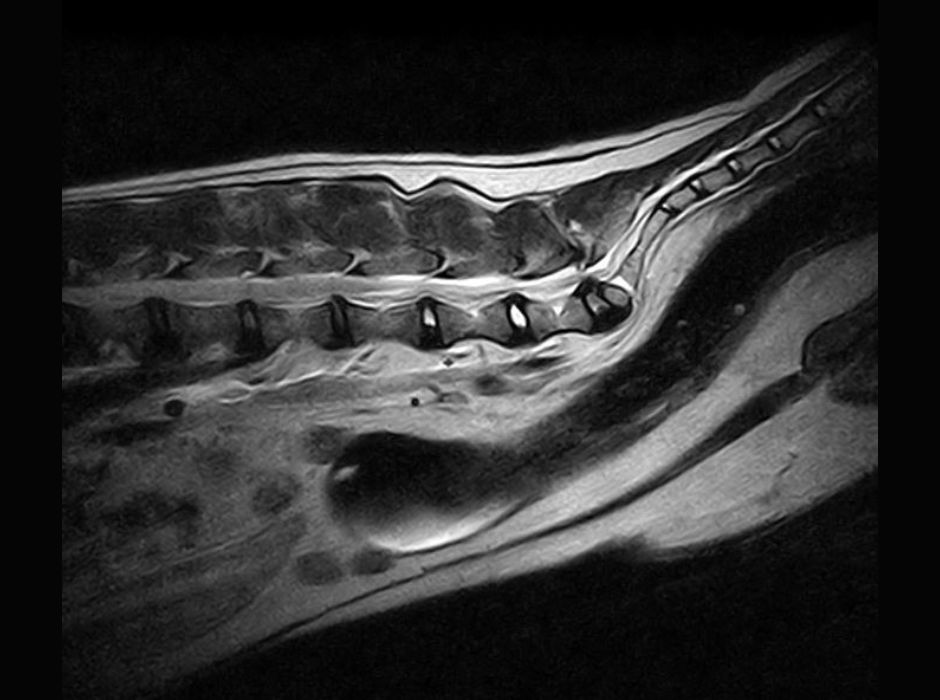

Thanks to detailed initial training and ongoing support, performing MRI examinations did not take long to learn, and Dr Sandra Gerhard, a specialised veterinary physician, has been part of our team since 2011. With the help of further training opportunities, specialised courses, and exchanges with other experts, knowledge and skills are being continuously improved. Thanks to specially designed coils and the open structure of the system, it is possible to position and examine animals of various types and sizes quite easily. We have benefited from excellent support here too.